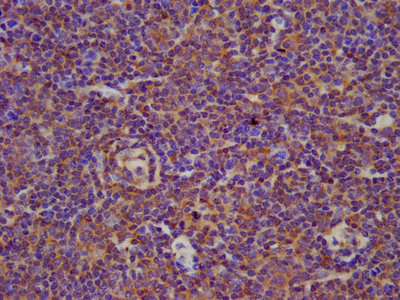

IHC image of CSB-PA002701LA01HU diluted at 1:100 and staining in paraffin-embedded human lymph node tissue performed on a Leica BondTM system. After dewaxing and hydration, antigen retrieval was mediated by high pressure in a citrate buffer (pH 6.0). Section was blocked with 10% normal goat serum 30min at RT. Then primary antibody (1% BSA) was incubated at 4°C overnight. The primary is detected by a biotinylated secondary antibody and visualized using an HRP conjugated SP system.